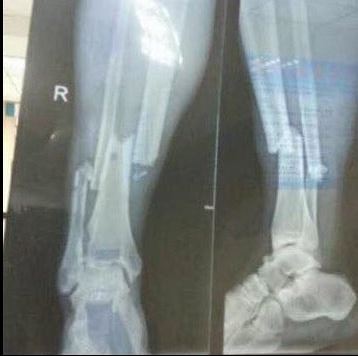

En ese instante, el atacante de 30 años intentó girar sin lograr ejecutar el movimiento. Lamentablemente su rival tropezó con él golpeando la parte baja de su pierna. ¿Qué pasó? Con la caída, el atleta chino le destrozó la tibia y peroné.

Cabe señalar que el delantero que era el goleador de la liga con 14 tantos, podría estar cerca de 8 meses fuera de la actividad.